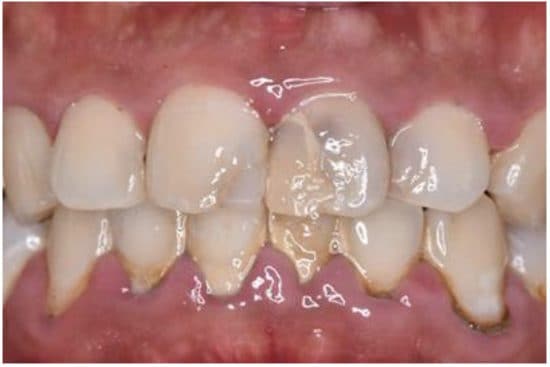

・黄ばんだ歯

・歯並びの乱れ

・口臭

・歯が欠けている

・歯茎が不健康

これらはすべて「だらしない」「自己管理ができない」という印象につながります。営業、接客、管理職、メディアに出る仕事ほど、口元の印象=評価と言っても過言ではありません。

例えば、営業に来た人が口臭が強く、黄ばんだ歯に、不健康な赤黒い歯茎だったらみなさんはその商品やサービスを取り入れようとはなかなか思えないはずです。人は、7秒以内に、この人から買うかを無意識に決めているからだと言われています。